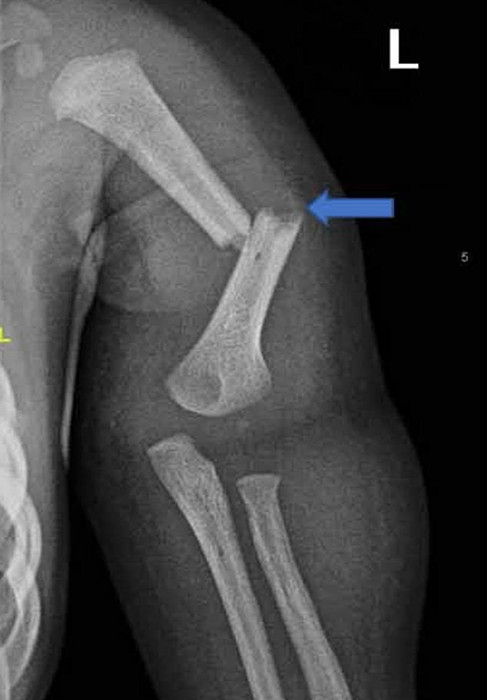

据报道,这起虐童事件于2017年2月曝光,当时这名男婴因手臂骨折被送往医院。这对夫妇向皇家萨塞克斯郡医院的医生谎报了男孩的痛苦以及他受重伤的原因,声称孩子被地毯凸起的一角绊倒了。后来医院发现男孩的伤势十分严重,肋骨骨折20处,膝盖、脚踝和都有骨折。儿科医学专家获取的证据显示,这些伤害是由强力所致,男孩骨折处是由于故意扭转、挤压造成的。医院确认骨折是在孩子被送到医院之前的四到六周之间造成的。